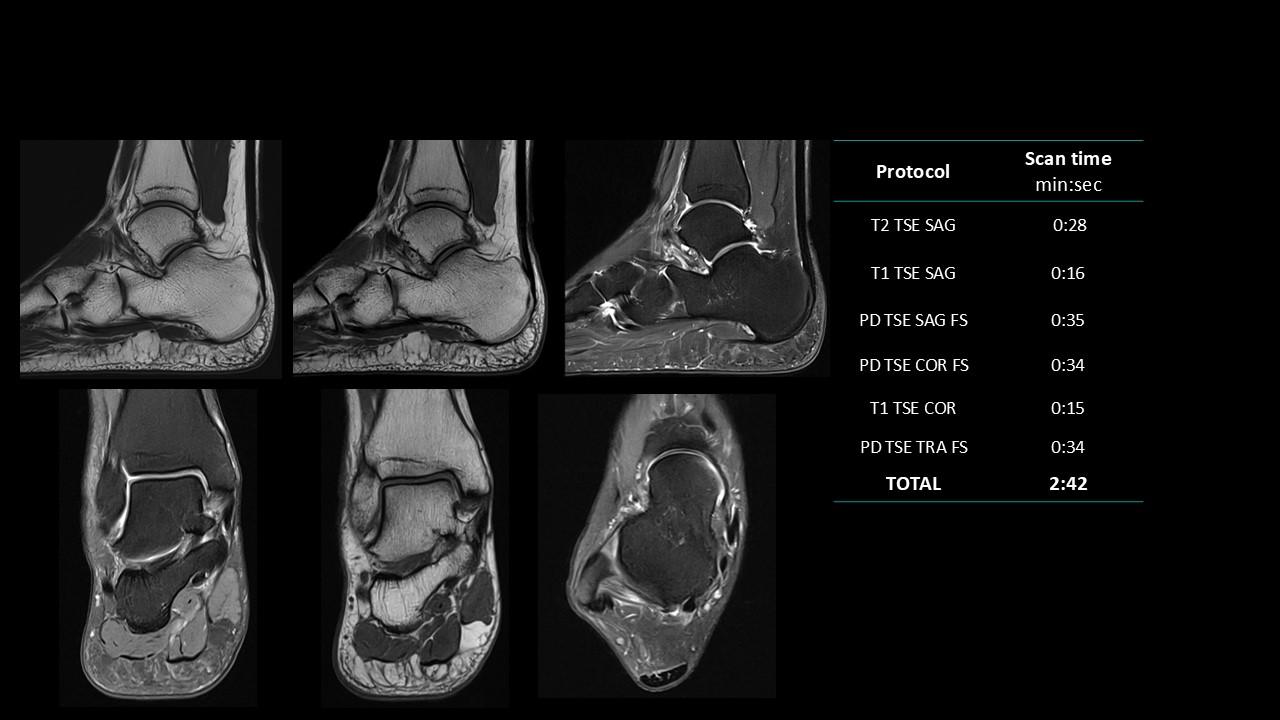

The Deep Resolve protocols are a set of advanced 3T MR imaging protocols designed to achieve high-quality diagnostic imaging with significantly reduced acquisition times.

Enabled by Deep Resolve, the AI-powered image reconstruction technology, these protocols deliver high-quality scans in approximately three minutes across a wide range of anatomical regions.

Developed and meticulously evaluated by Dr. Seong-ho Lee of Leaders Radiology Hospital in Seoul, Korea, the protocols integrate deep learning technology to enhance imaging efficiency while maintaining diagnostic detail.

By reducing scan duration, they improve workflow efficiency and patient experience without compromising image quality.